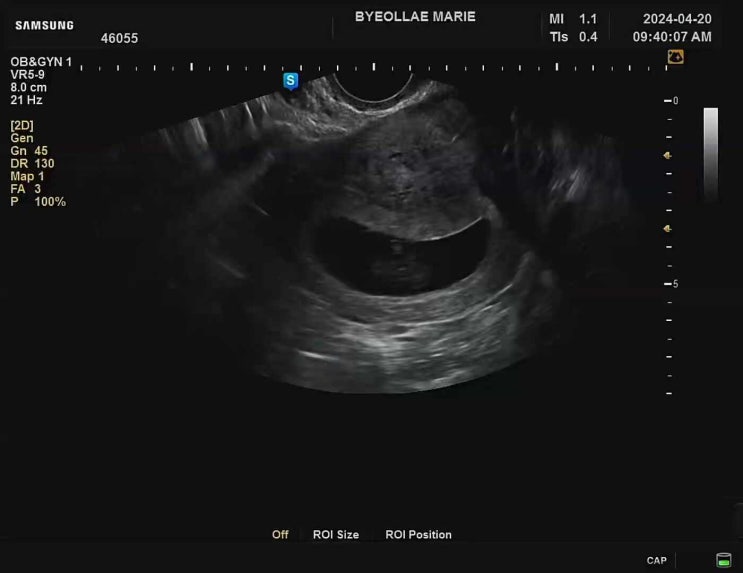

[다낭성 난소 증후군의 자연임신일기 : 26주 검진]입체초음파 + 공포의 임당검사 재검 후기

어느덧 26주 사실 이건 임당 재검 포스팅이다 나는 아무생각없이 26주검진을 갔다 이날 괜히 파워 걱정인형...